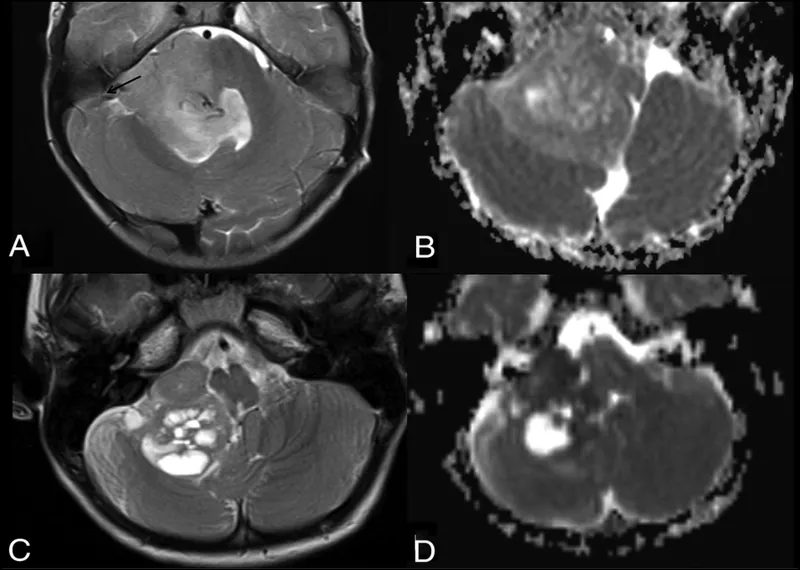

- Imaging: MRI with gadolinium contrast is the gold standard for diagnosis & surgical planning.

| Pilocytic Astrocytoma (Grade I) | - Most common pediatric brain tumor. - Biphasic pattern: dense fibrillary areas + loose microcystic areas. - Rosenthal fibers (eosinophilic corkscrew bodies). - GFAP positive. | Cerebellum |

| Medulloblastoma (Grade IV) | - 2nd most common; most common malignant type. - Small, round, blue cells. - Homer-Wright rosettes. - Highly radiosensitive. | Cerebellum (Vermis) |

| Ependymoma | - Arises from ependymal cells lining ventricles. - Perivascular pseudorosettes. - Often presents with hydrocephalus. | 4th Ventricle |